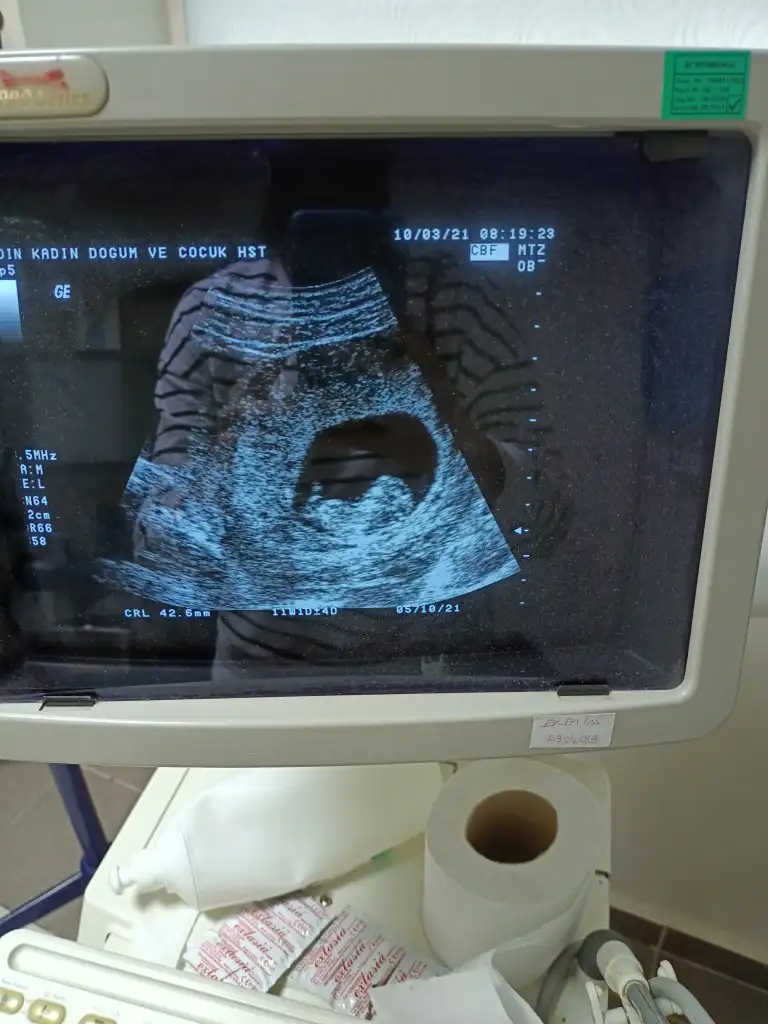

Merhaba arkadaşlar devlet hastanesine gittim bugün 11+1 di ikili tarama testi için Aslında haftaya özele de gidicem 12+3 olacak o zaman da kan vericem. Devlet özel birlikte götürüyorum. İyi görünüyor dedi doktor devlette olunca çok da bişey soramıyorsun . Başından beri erkek hissediyorum ama cinsiyet tahmini yapacak arkadaşlar varsa çok sevinirim. Herkese sağlıklı günler

Eklentiler

• 11.webp

45,3 KB · Görüntüleme: 91

45,3 KB · Görüntüleme: 95